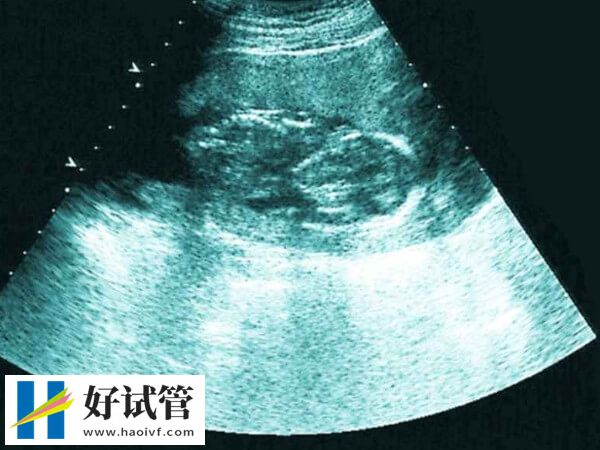

- 5. 子宫停止增大:当胚胎停育后,体内的激素水平会发生变化,导致子宫不再继续增大。这种情况可以通过超声波检查来确认,表现为子宫大小与怀孕周数不符。